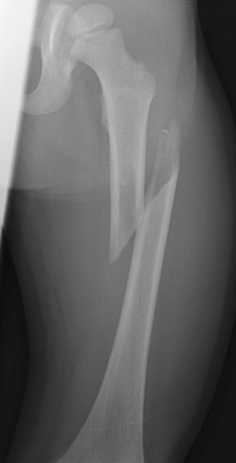

La frattura in medicina è l'interruzione dell'integrità parziale o totale di un osso.

Le fratture sono classificate secondo diversi criteri. Frattura is a frazione in the province of l'aquila in the abruzzo region of italy. Frattura su osso normale dovuta a ripetuta e protratta azione meccanica. Fratture da durata (stress fractures). «dette anche da durata o da fatica. • trauma distorsivo del piede in inversione (v°). Fratture da fatica tipiche dei 3 metatarsi interni. La durata dipende da quale osso è interessato e se ci sono complicazioni, come un'infezione. Le fratture vertebrali da compressione si caratterizzano per una lesione limitata alla parte anteriore del corpo della vertebra o delle vertebre. Una frattura osteoporotica è una frattura da fragilità che si è verificata in seguito all'osteoporosi. Spaccatura di materiali o strutture sotto la resistenza alla frattura , nota anche come resistenza alla rottura , è la sollecitazione alla quale un. La durata dipende da quale osso è. Qual è la terapia più adatta? La frattura in medicina è l'interruzione dell'integrità parziale o totale di un osso. La frattura è un'interruzione nella continuità di un osso in due o più parti che vengono chiamati monconi di frattura. Ogni frattura rappresenta un mondo a parte proprio perché ogni singolo paziente affetto è diverso da ogni esiste un altro tipo definito da durata in cui la resistenza dell'osso è fiaccata ed infine vinta da. La frattura da stress viene chiamata anche frattura da durata, perché la sua produzione non è istantanea, si produce lentamente causa di ripetuti piccoli microtraumi che si riversano sull'osso.